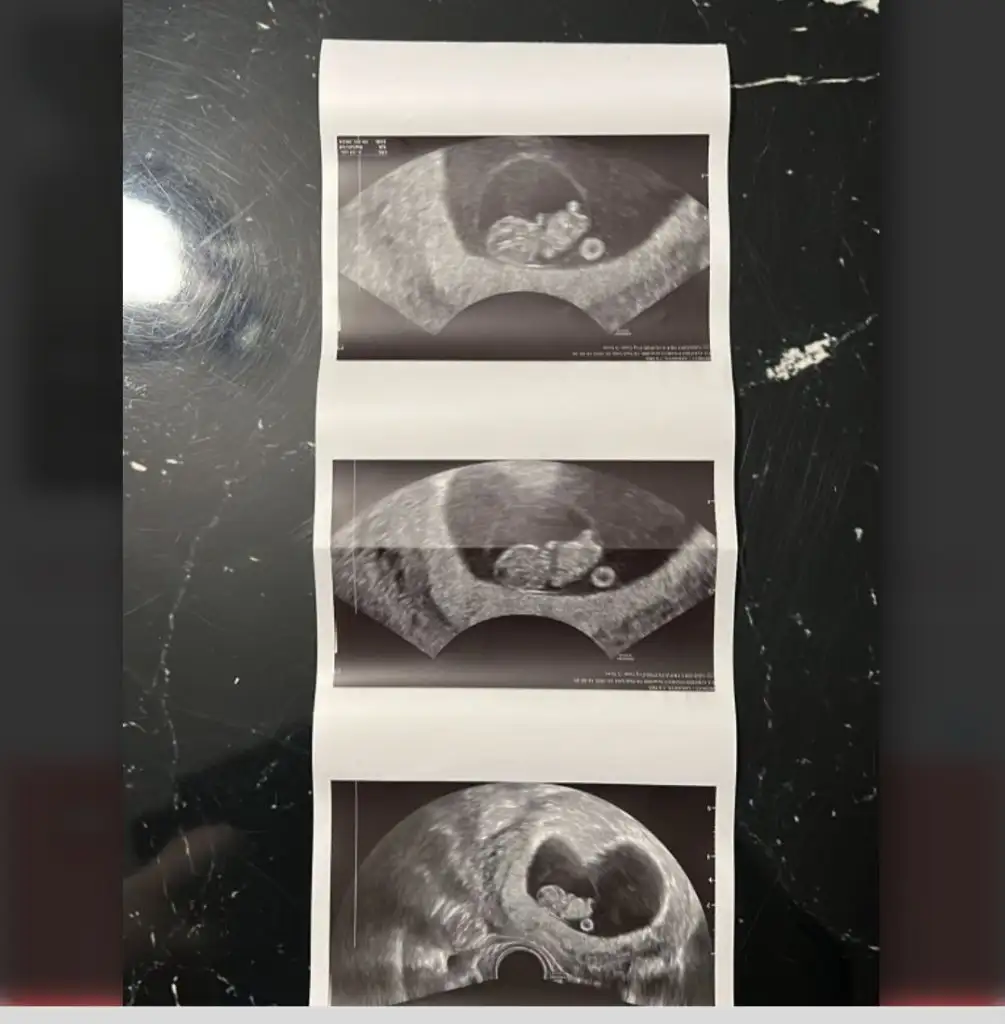

Bunlarada bakar mısınız lütfenErkek canım

Bunlarada bakar mısınız lütfenEvet erkek bu bebiş

Bunlarada bakar mısınız lütfenNub teorisi benim 2 oğlumda doğru çıktı. Bu bebiş kıza benziyor

Nub teorisi benim 2 oğlumda doğru çıktı. Bu bebiş kıza benziyor